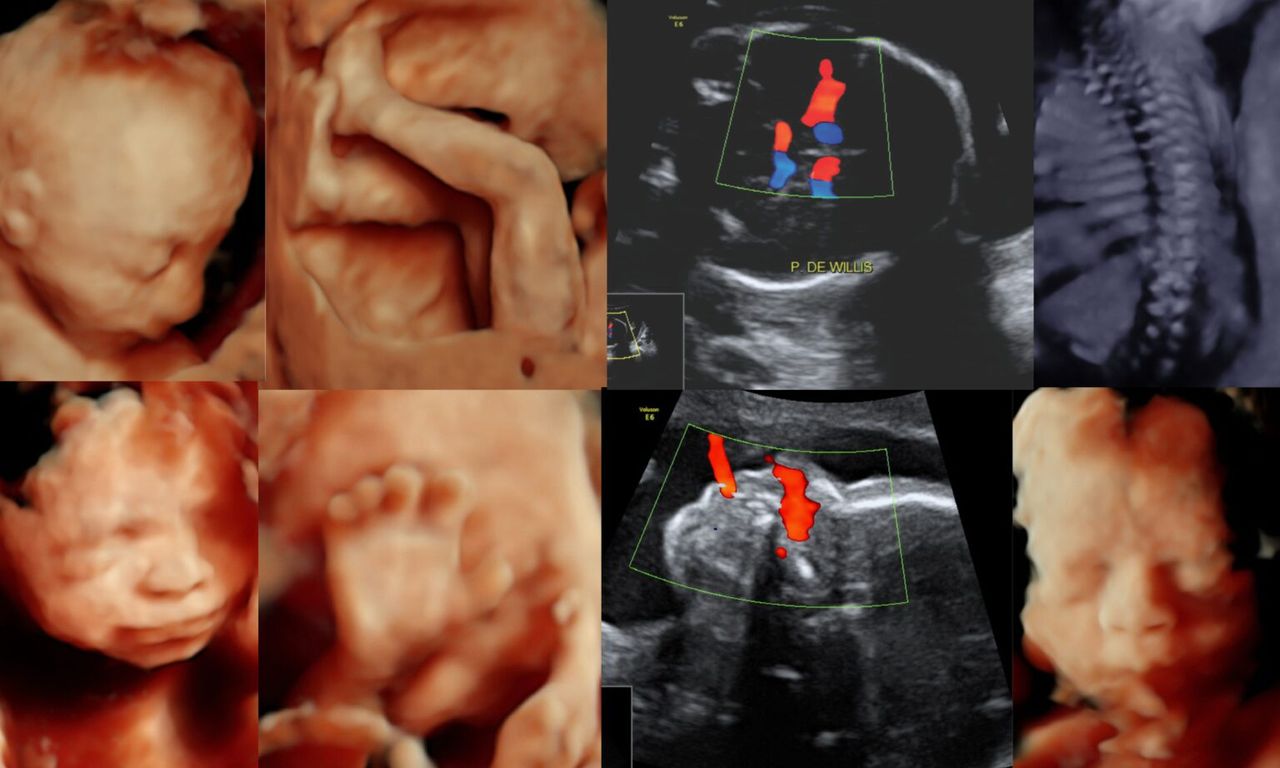

Interpretación por imágenes por ultrasonido, tomografía, resonancia magnética, estudios especiales y segunda opinión diagnostica

Fotos y videos

Destacados

Servicio de Radiologia e intervencion, cualquier duda preguntame por un mensaje.

• HOSPITAL POLANCO ZULMEDICA IMAGEN CONSULTORIO 8 Ultrasonido 4D (HD-live)  •